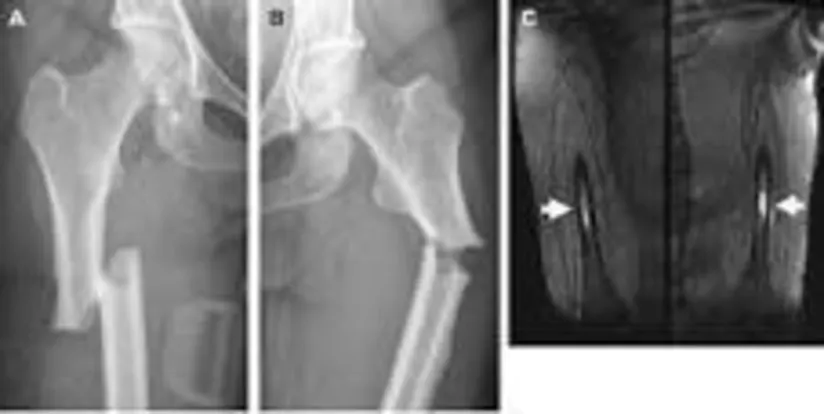

不典型股骨骨折影像

典型的x光片通常不会显示出股骨应力性骨折,所以如果x光片没有显示出骨折,就需要进行MRI或CT扫描。大多数情况下,骨折一定是低能性创伤导致的骨折是在摔倒前骨折的。如果核医学试验显示这种类型的骨折,那么你将有一个诊断AFF。